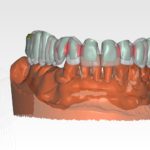

Bridge provisoire transvissé réalisé au laboratoire :

Ce bridge a été réalisé en technique d’impression numérique avec création de la fausse gencive par maquillage de surface